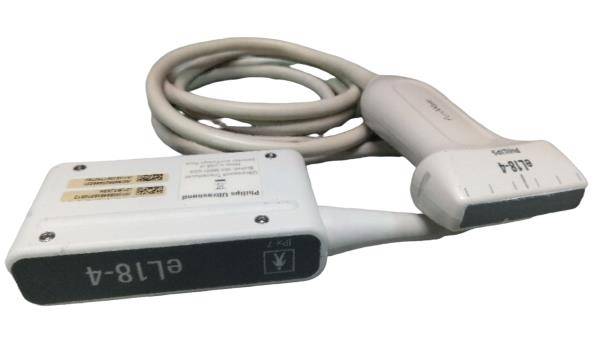

DIAGNOSTIC ULTRASOUND MACHINES FOR SALE

SonoSite S-Cath Ultrasound System WITH CART

Sale price$ 8,610.00